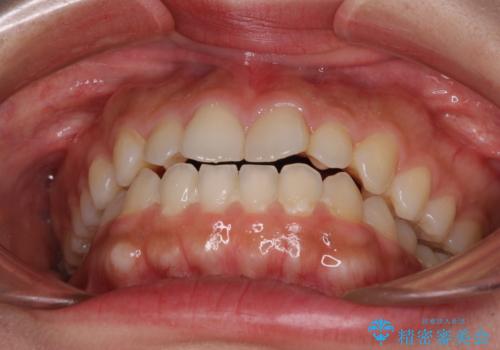

- 上顎前歯の叢生を気にして来院された患者様です。

下顎前歯や上下奥歯の咬み合わせには殆ど問題がないため、上顎前歯のみを矯正する治療を提案しました。

ワイヤー装置でもインビザラインでも可能でしたが、前歯のみをきれいに排列するのであればインビザラインの方が仕上がりが良いので、インビザライン・ライトにて治療を行うこととしました。

インビザライン・ライトは、製作できるアライナーの枚数に制限があるため、移動可能な量に限りがあります。

一方で、半年から1年程度で治療を終えることができるため、軽度の歯列不正の患者様には大変お勧めです。